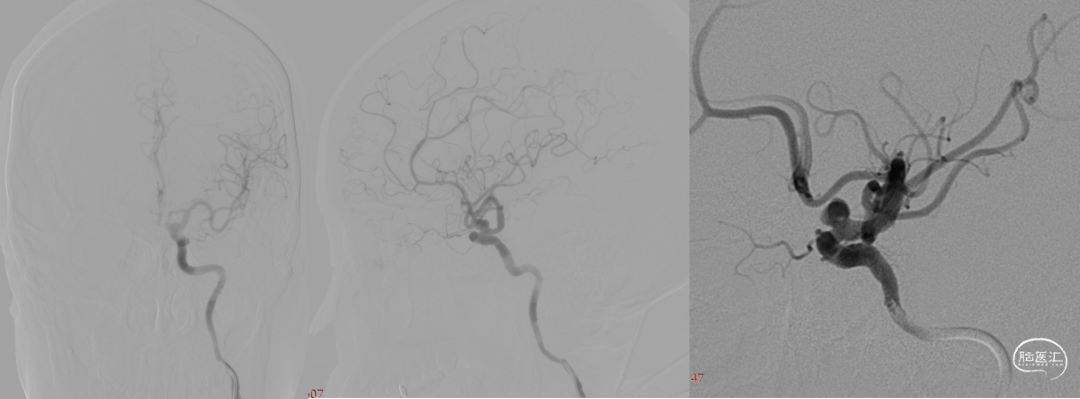

术前造影:

右颈

左椎

6F Navien到位,工作位造影。

Echelon 10微导管预留在动脉瘤瘤腔内,Phenom 27内输送J-Tube™ 4*20血流导向密网支架,顺畅到位,头端打开良好。

J-Tube™打开过程-整体显影性能良好。J-Tube™血流导向密网支架整体释放,贴壁良好。

疏松填塞弹簧圈后正侧位造影。